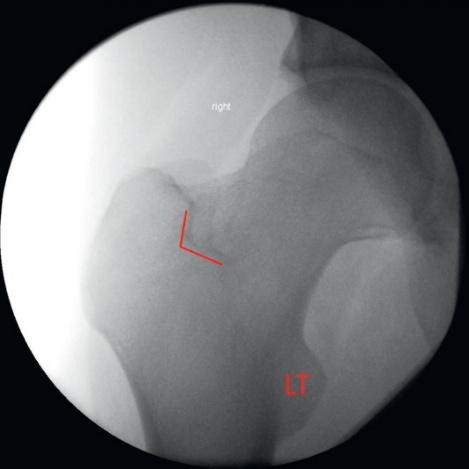

由于对侧髋关节与手术侧影像重叠,可能导致成像判读困难。此外,既存的对侧植入物可能进一步干扰影像学评估。通过仔细比对股骨头尺寸差异(图21与图22),可有效实现鉴别诊断。

什么是c型臂术中透视骨科精读 | 股骨近端骨折的转子区域与矢状面力线术中透视技巧_https://www.jmylbn.com_新闻资讯_第21张

图21

什么是c型臂术中透视骨科精读 | 股骨近端骨折的转子区域与矢状面力线术中透视技巧_https://www.jmylbn.com_新闻资讯_第22张

图22

如下方术中影像所示,最靠近影像增强器(距射线发射源最远)的股骨头显像较小且包含植入物。相反,距离射线发射源最近的股骨头显像尺寸显著增大(图23)。

什么是c型臂术中透视骨科精读 | 股骨近端骨折的转子区域与矢状面力线术中透视技巧_https://www.jmylbn.com_新闻资讯_第23张

图23